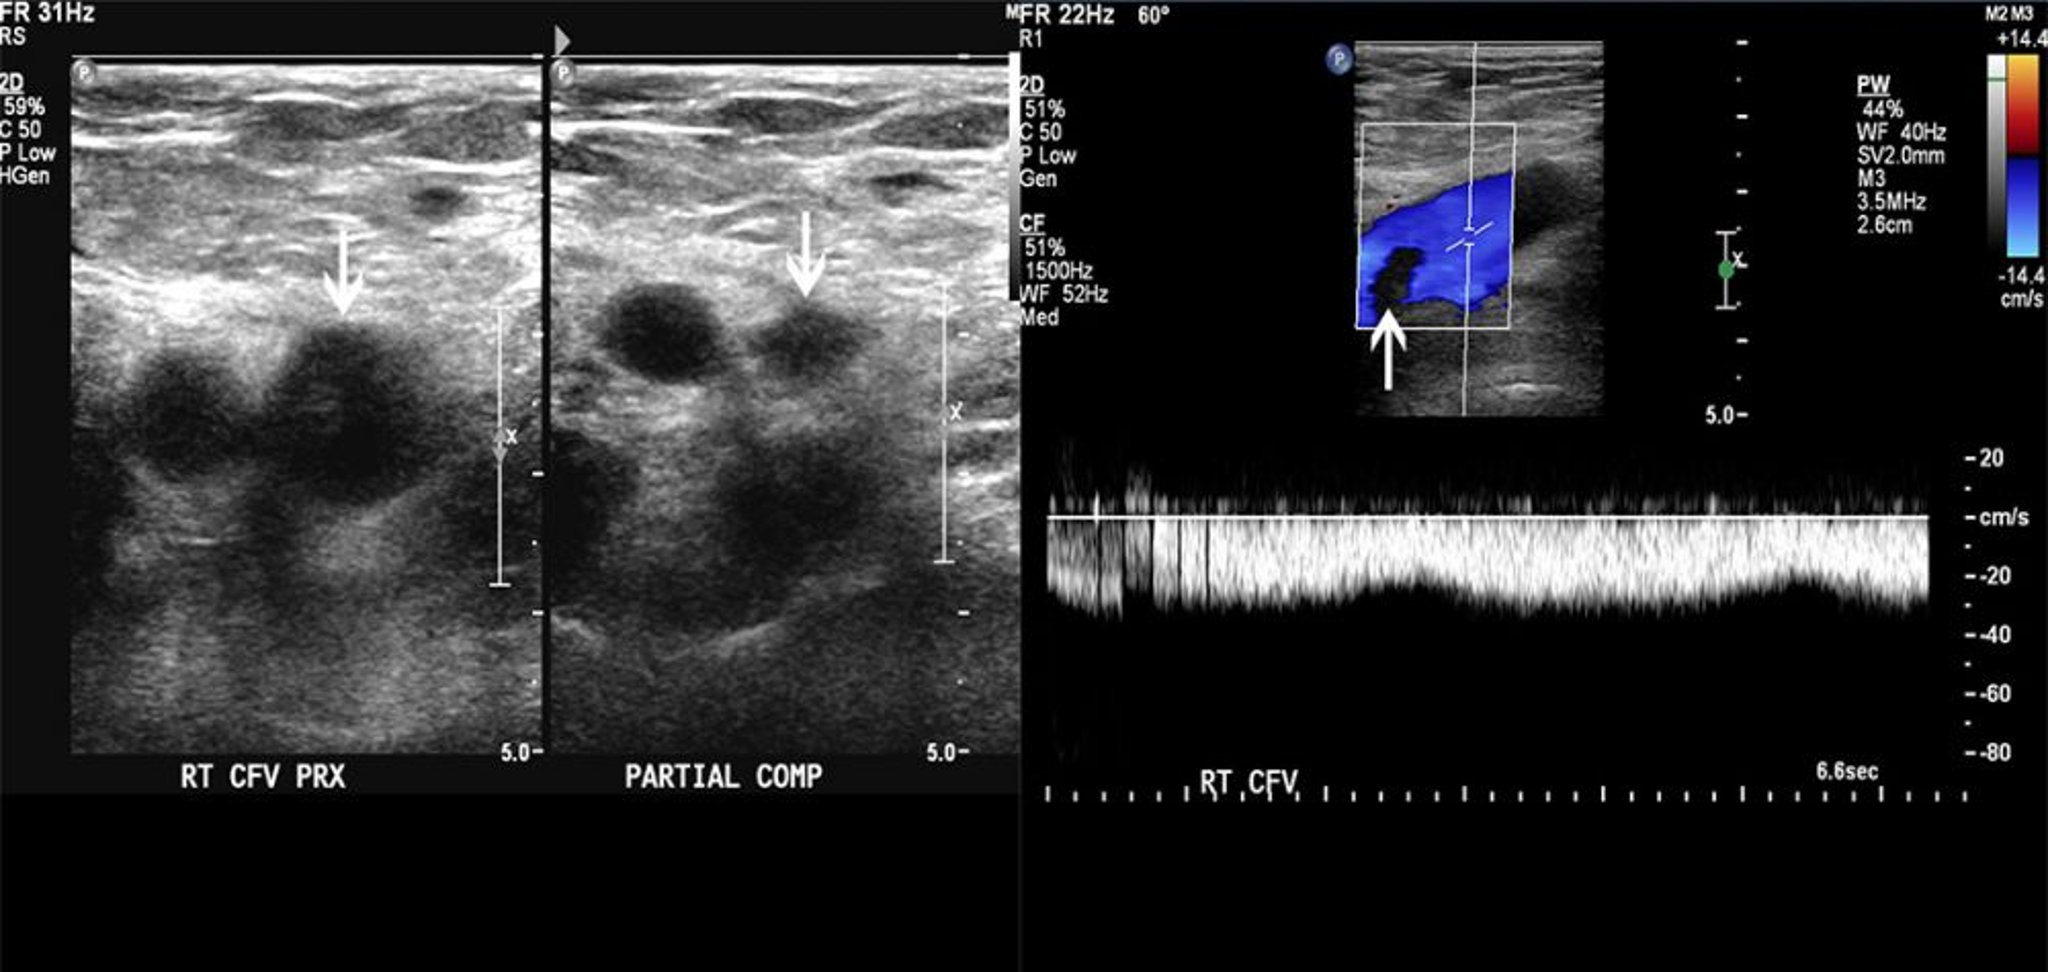

Sonographie

Die Sonographie weist Thromben nach durch eine direkte Visualisierung der venösen Begrenzung und durch den Nachweis einer veränderten Kompressibilität der Vene oder im Fall von Doppler-Flussmessungen den Nachweis eines veränderten venösen Blutflusses. Der Test hat eine Sensitivität von > 90% und eine Spezifität von > 95% für femorale und popliteale Venenthrombosen, ist aber weniger akkurat bei iliakalen oder Beckenvenenthrombosen (1).